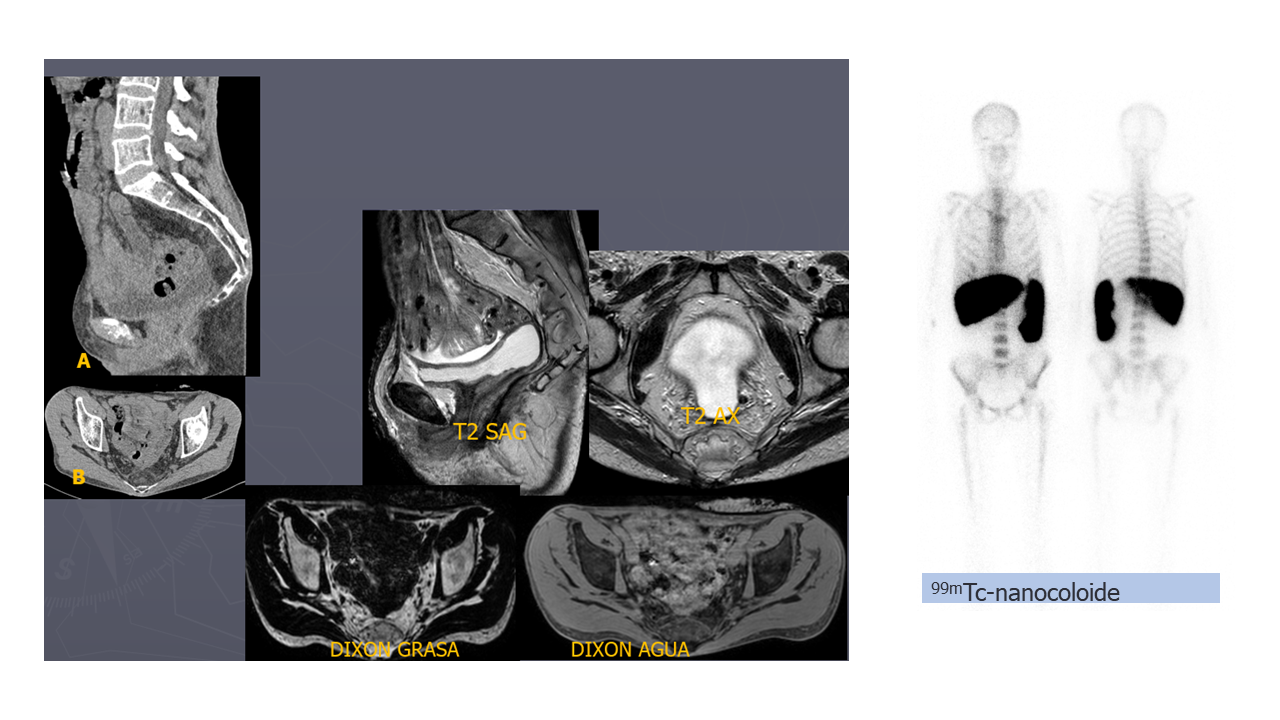

Figura 1. RM y TC pélvico: Ocupación del espacio presacro por una lesión lobulada de aspecto encapsulado de 5 cm, discretamente heterogénea, con un contenido fundamentalmente graso. La lesión se apoya en la cortical anterior del sacro sin signos de destrucción ni infiltración ósea.

Figura 2. Gammagrafía de la médula ósea tras administración de 99mTc-nanocoloide de albúmina:

Captación fisiológica hepatoesplénica y en la médula ósea, sin captación de la lesión presacra.